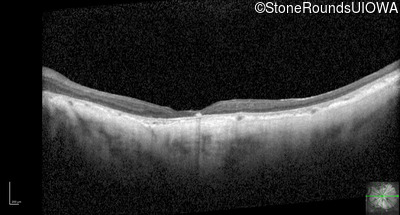

Optical Coherence Tomography - Right - 10/200 -2 sc

Exemplar / OCT Stack